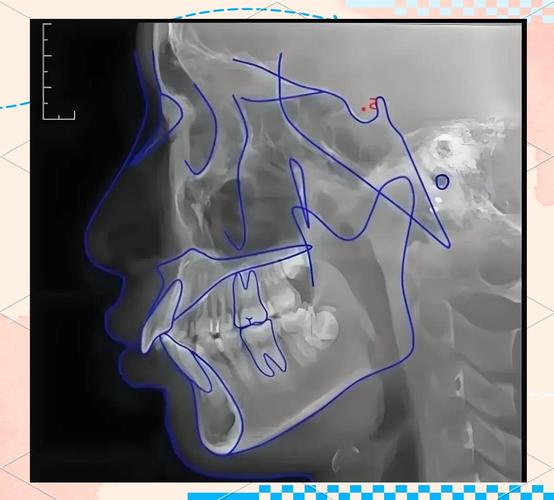

SN MP角度由两条平面构成:SN平面(颅底平面)和MP平面(下颌平面),SN平面连接蝶鞍中心点(S点,蝶鞍前后径的中点)与鼻根点(N点,额鼻缝与正中矢状面的交点),代表颅底的前后方向,是颅面部稳定的参考平面;MP平面通常连接颏下点(Me点,下颌骨最下点)与下颌角点(Go点,下颌角最下点),反映下颌骨下缘的倾斜方向,体现下颌相对于颅底的垂直向位置关系,该角度为SN平面与MP平面在颅底侧位片上的夹角,角度大小直接反映下颌平面的倾斜程度:角度越大,下颌平面越陡峭(下颌向下后旋转),面部垂直向高度增加;角度越小,下颌平面越平缓(下颌向上前旋转),面部垂直向高度减小。

SN MP角度的测量需依赖标准化的头颅侧位片,具体步骤如下:

- 拍摄头颅侧位片:患者取自然头位,眶耳平面(FH平面,与地面平行)与定位架贴合,确保图像无失真。

- 标记标志点:在侧位片上定位S点(蝶鞍中心)、N点(鼻根)、Me点(颏下)、Go点(下颌角),需结合解剖结构反复确认,避免误差。

- 绘制平面:连接S、N点绘制SN平面;连接Me、Go点绘制MP平面(部分研究采用下颌下缘切线作为MP平面,需统一标准以保证结果可比性)。

- 测量角度:使用量角器或专业测量软件,以SN平面为基准,测量其与MP平面的夹角(通常取锐角,若为钝角需以180°减去该值)。

测量时需注意标志点的清晰度及图像的放大比例,必要时可重复测量取平均值,提高准确性。